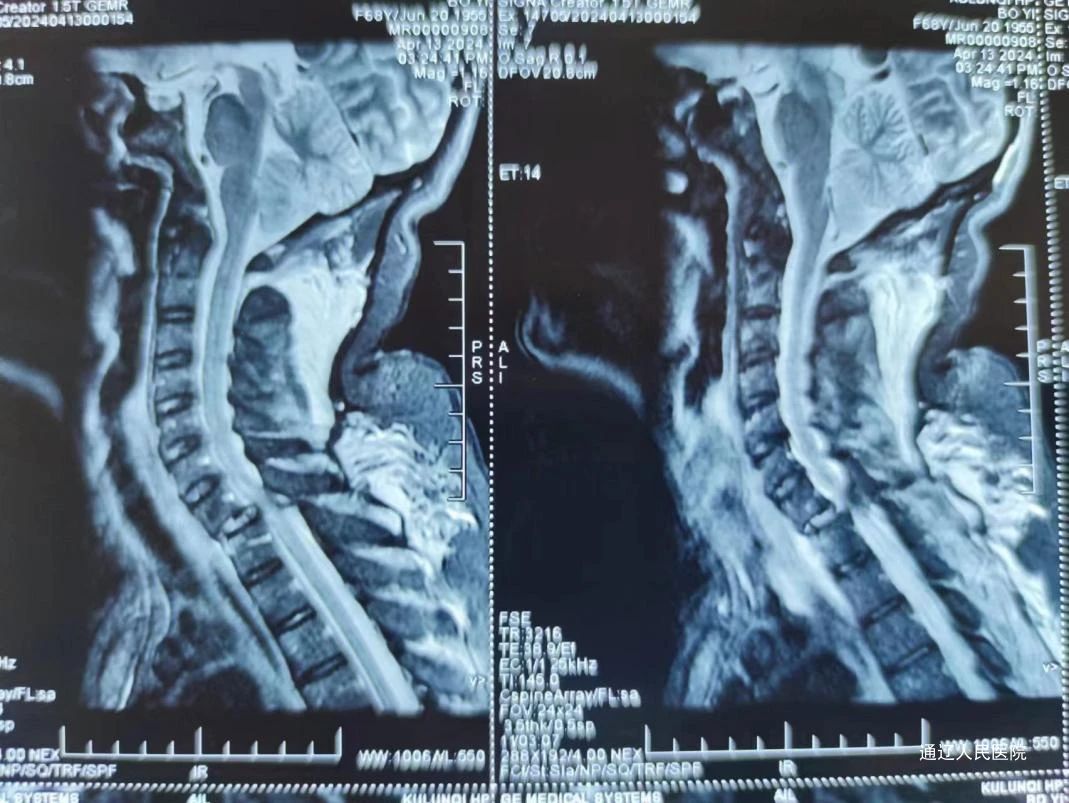

近日,我院脊柱外科在科室负责人房芳的带领下成功为一名颈7椎体骨折脱位合并截瘫的患者,施行了后入路颈椎骨折脱位切开复位减压植骨、颈椎侧块螺钉内固定、胸椎椎弓根螺钉内固定术,这项手术在骨科领域被认为是“三高”手术,即高难度、高风险、高要求,填补了我市技术空白。患者女性,68岁,因外伤致颈7椎体骨折脱位合并截瘫,由下级医院转院送至我院治疗。入院后,医院领导高度重视,迅速进行资源调配,保障及时抢救。我院医护团队立即展开积极对症处理措施,并迅速完善相关检查。考虑到患者年龄较大且病情严重,医务部组织了重症监护和麻醉团队等多学科开展联合会诊MDT。经过深入讨论和分析,专家们为患者量身定制了详尽的手术治疗方案,旨在最大限度地降低手术风险,确保患者安全。

术中减压充分、颈椎骨折脱位完全复位,内固定位置及牢固程度令人满意。在我院脊柱外科、手术室、麻醉科、ICU、输血科协力合作下手术顺利完成。术后患者生命体征平稳,双下肢感觉部分恢复。肢体可以活动。恢复康复训练后远期可生活自理。

颈胸交界处固定手术对于脊柱外科一直属于一个难点,由于在较小的颈椎和较大的胸段交界处有不同的过渡应力,靠近神经血管结构,以及复杂的解剖结构,在固定这些区域时必须极其小心和精确。作为通辽市首例颈椎胸椎联合固定手术,这项手术的成功实施,不仅体现了我院脊柱外科医生的精湛技艺,也为脊柱疾病患者带来了新的治疗希望,标志着我院脊柱外科在颈椎、高位胸椎疾病治疗方面,上了一个新的台阶。随着医学技术的不断进步,我院将不断引进和学习国际先进的医疗技术和理念,提升诊疗水平。同时,加强与国内知名医疗机构的合作,共同推动脊柱外科领域的发展,为患者健康保驾护航。